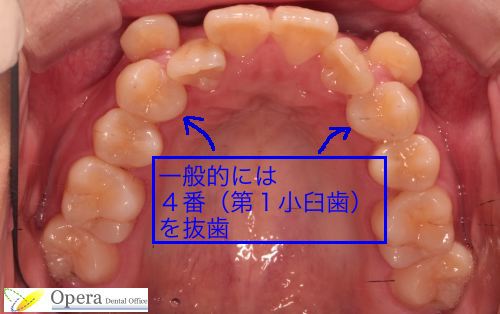

このように、著しく歯の並ぶスペースがない場合、以下の写真の矢印の歯:第一小臼歯を抜歯してスペースを作り、歯を並べることが多いです。

一般的には真ん中の歯から数えて4番目、第一小臼歯を抜歯し、それによってできた空隙を利用して歯並びを整えていきます。

歯並びを右上・左上・左下・右下の4ブロックに分けたとき、

1ブロックにつき前歯2本・犬歯1本・小臼歯2本・大臼歯2本

となります。

このような症例では多くの場合、矢印で示した第一小臼歯(4番)という歯を抜歯してスペースを作り、歯を並べていきます。